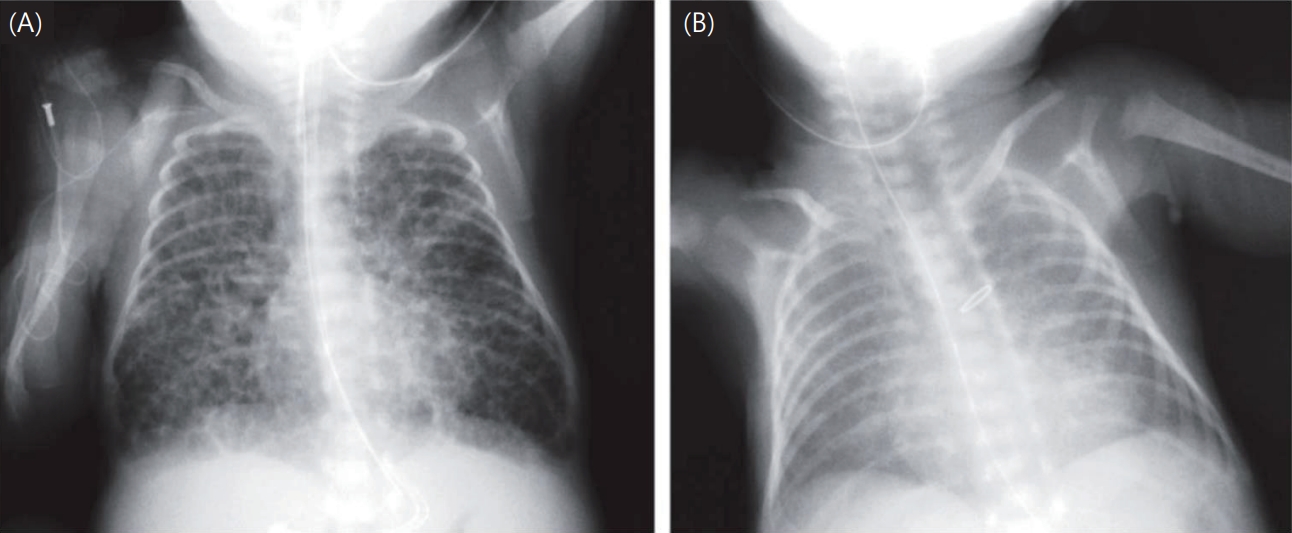

Exposure factors were determined according to the revised Japanese BPD classification. SGA was defined as a BW below the 10th percentile for gestational age according to the Japanese neonatal anthropometric reference curves [15]. These population‑specific values were used because harmonized international birth‑weight z scores were unavailable in the original RCT dataset. Chest radiographs at 28 days were evaluated, and infants judged as having bubbly/cystic changes in the original RCT by participating centers were classified as positive in the present analysis. Representative examples of bubbly/cystic and non‑bubbly chest radiographs are shown in Fig. 1 [16]. In the original RCT, detailed documentation about who interpreted the radiographs and under what conditions were lacking, so the number and specialties of readers and whether the readings were blinded are unknown. Because the images were not available for review, interobserver reproducibility could not be assessed. This limitation reflects real‑world practice in Japan, where neonatologists rather than radiologists typically interpret NICU chest radiographs, and standardized blinded procedures are not routinely used [9]. CAM was defined as acute inflammatory cell infiltration in the amnion, subchorion, or chorion on placental histopathology. RDS was defined as respiratory distress from birth combined with characteristic chest radiographic findings, with surfactant replacement therapy administered as needed. PDA was diagnosed via echocardiography. Data on maternal steroid use and other clinical background variables were extracted from the original RCT database. Potential confounders included BW, GA, sex, 5-minute Apgar score, maternal steroid use, RDS, and PDA. Continuous variables were expressed as mean±standard deviation or median (interquartile range) and compared using the t test or Mann-Whitney U test, depending on normality. Categorical variables were compared using the chi-square test or Fisher exact test. For the primary outcome of severe BPD, univariate and multivariate logistic regression analyses were conducted to calculate odds ratios (ORs) with 95% confidence intervals (CIs). Initially, univariate analyses were conducted to evaluate the association between each candidate variable and severe BPD. Variables with a value of P<0.10 in the univariate analysis or considered clinically relevant (including antenatal corticosteroid exposure) were entered into the multivariate model, alongside classification-related factors (SGA, bubbly/cystic chest x-ray findings, and CAM). A subgroup analysis was also conducted for infants born at <27 weeks’ GA to evaluate the association between BPD subtypes and severe BPD. A 2-sided value of P<0.05 was considered statistically significant. In addition, the predictive performance of the final multivariable logistic regression model was evaluated. Discrimination was assessed using the area under the receiver operating characteristic (ROC) curve, and calibration was examined using the Hosmer-Lemeshow goodness-of-fit test. All statistical analyses were conducted using IBM SPSS Statistics ver. 29.0 (IBM Co., USA).

Bubbly/cystic changes on chest x-ray were identified as the strongest predictor. Chest radiography, which is generally performed in the NICU, provides a surrogate marker of structural injury without additional burden [19]. These radiographic findings reflect parenchymal heterogeneity, hyperinflation, airway obstruction, and microalveolar rupture, all of which have been demonstrated to prolong oxygen and ventilator dependence [16,20]. The identification of this factor as an independent risk indicates the clinical rationale for early intervention strategies based on imaging, such as optimization of lung volume settings, secretion management, and lung-protective ventilation.

Fig. 1.

Representative chest radiographs illustrating the bubbly/cystic appearance used in the new Japanese bronchopulmonary dysplasia classification (16). (A) Chest radiograph showing a bubbly/cystic pattern (positive). (B) Chest radiograph showing a nonbubbly pattern (negative).